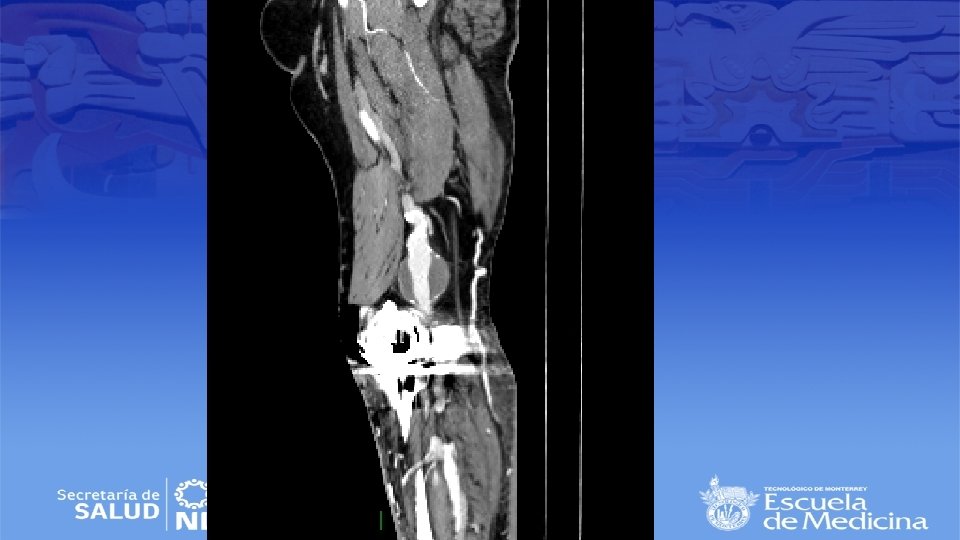

Angiotac

Impresión Diagnóstica • IDX: Aneurisma Poplíteo bilateral

Diagnostico • Ultrasonido Doppler, Angiotac, angioresonancia • Arteriografía es mas apropiada para sintomatología aguda